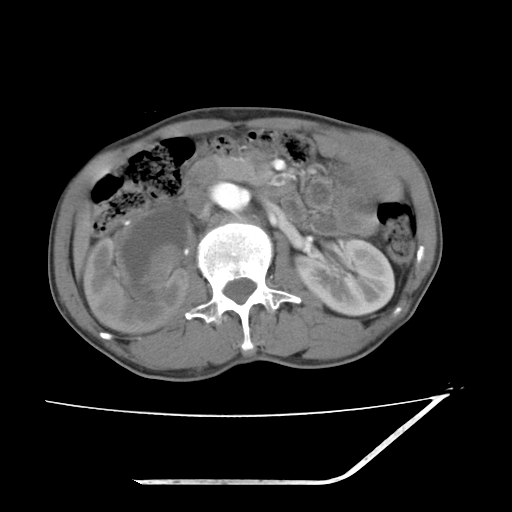

增强

考虑右肾盂癌,肾动脉受侵,右肾功能减退,右肾盂输尿管积水,管壁增厚,考虑种植转移,应该把下面扫完的

支持右侧肾盂癌伴肾静脉瘤栓形成可能性大,右肾结石.肝右叶后段低密度影,不除外转移.

右肾囊实性占位,支持肾癌,窗宽窗位不是很理想

右肾盂旁ca并肾静脉瘤栓形成/肾功能降低。

右肾结石。

支持 右侧肾盂癌伴肾静脉瘤栓形成可能性大,右肾结石;肝右叶后段低密度影,不除外转移。

1.右侧肾盂癌伴肾盂积水。

2.肾脏功能减退,原因有:(1)肾动脉受侵。(2)肾静脉受侵(3)肾积水,等。本例,肾动脉显影较好,但受压明显;肾静脉无明显显示,受压或静脉癌栓,下腔静脉腔内未见明显充盈缺损。